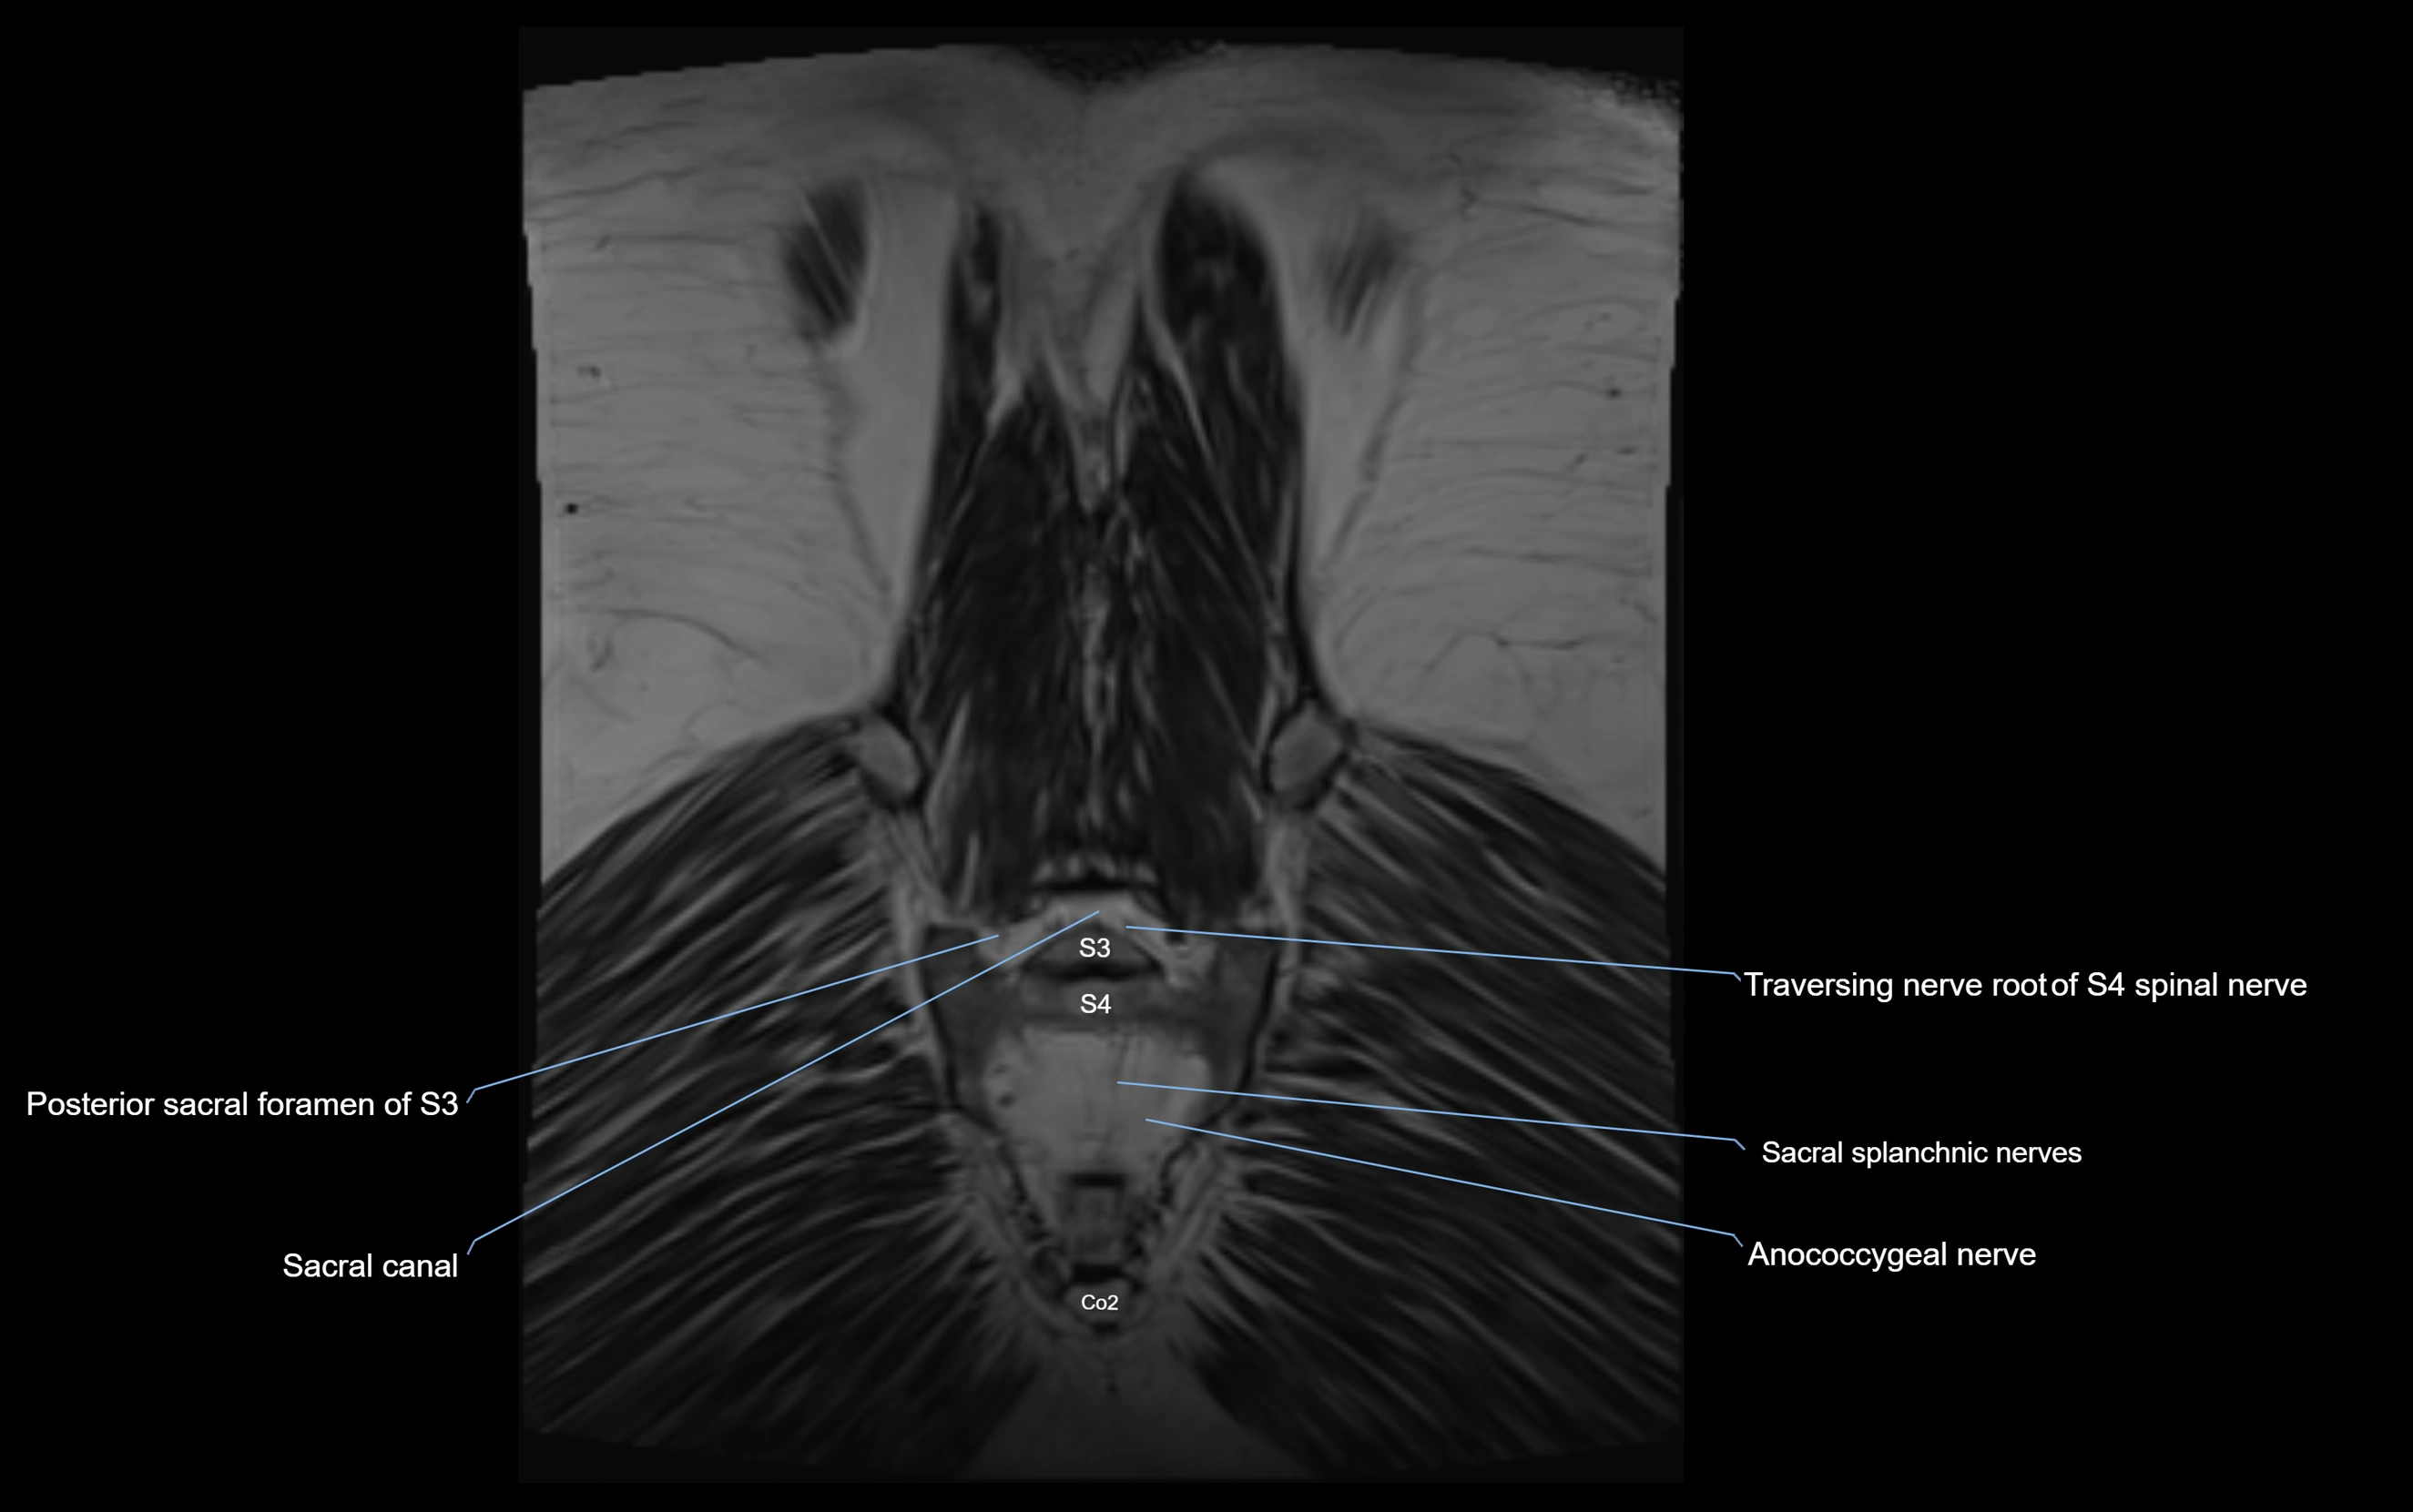

MRI image

image